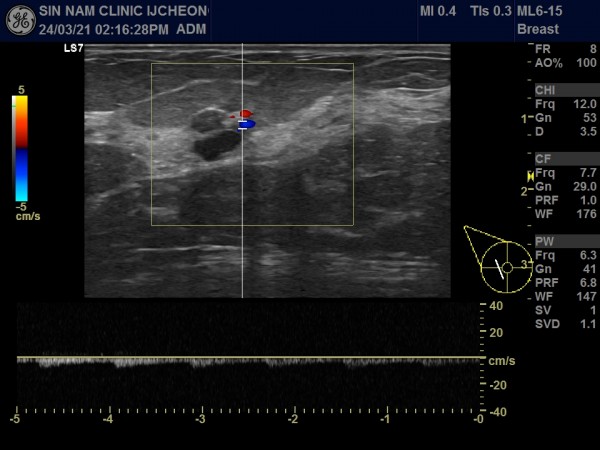

아래 사진 자료의 환자분은 50세 여성으로 국가검진으로 본원에 내원해주셨습니다.

유방촬영中 혹이 발견되어 초음파 검사를 시행하였습니다.

혹이 1.5cm 정도였습니다.

만져지거나 분비물이 나오는 증세는 없었습니다.

혹의 유두에 근접해 있고, 유관과 연결되어 있어 혈류가 증가된 소견이여서 유방암보다는 관내유두종의 가능성이 높아 대학병원으로 전원해 조직검사를 시행해서 관내유두종으로 진단받고 수술하셨습니다.